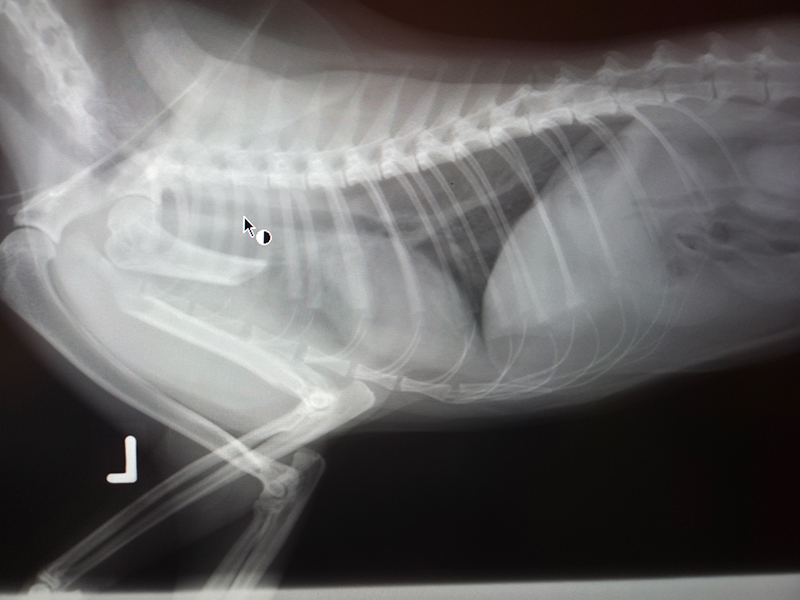

In der Tierarztpraxis bestätigte sich die schlimme Vermutung: Chief hatte einen Bruch des Oberarmknochens. Wenigstens zeigte die Untersuchung, dass er keine weiteren sichtbaren Frakturen und keine inneren Blutungen im Bauch- oder Brustraum hatte. Er bekam sofort Schmerzmittel und wurde notfallmässig versorgt.